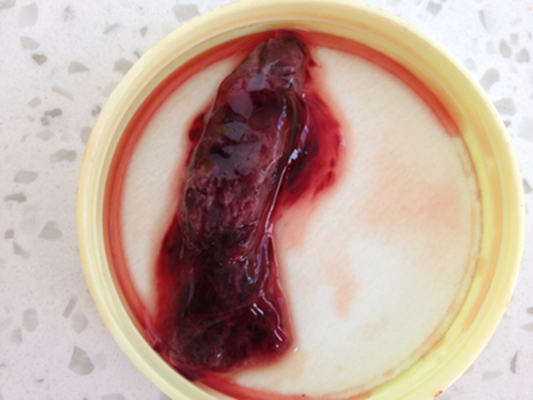

流產圖片

流產掉下來的孕囊

流產掉下來的孕囊

流產掉下來的孕囊

流產掉下來的孕囊

流產掉下來的孕囊

流產掉下來的孕囊

流產掉下來的孕囊

流產掉下來的孕囊

流產掉下來的孕囊

流產掉下來的孕囊